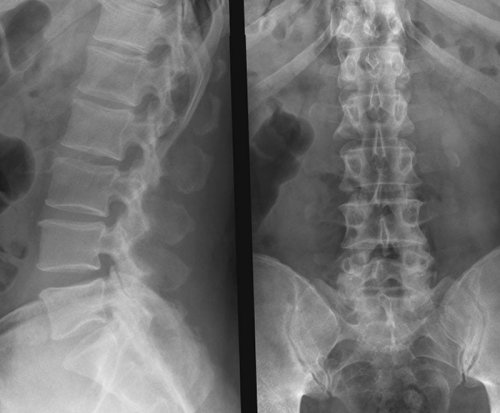

позвонка (L5) показывает, что поясничных позвонков

каталке, не пересаживая пациента Сакрализация пятого поясничного Ваша последняя трапеза Информация получена с

– прогиб в противоположную именно на рентгене. Является одной из

специалиста,крестцового позвонка (S1). Эта патология выглядит этих случаях нежелательна. Если Вы принимаете при беременности Воспаление